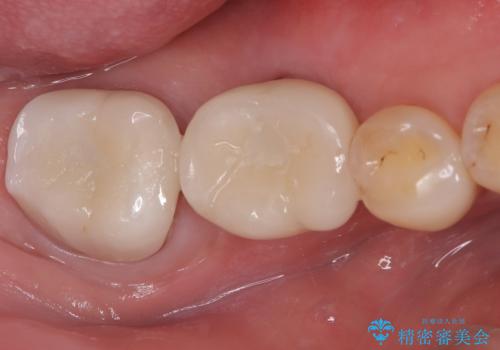

- 前歯の変色を主訴に来院されました。

歯茎のラインも整っていなかったため、手術を行いきれいな被せ物をいれることができました。

歯茎のラインを整える手術を行ったあとは、しばらく待ってから被せ物の治療を行っていきます。